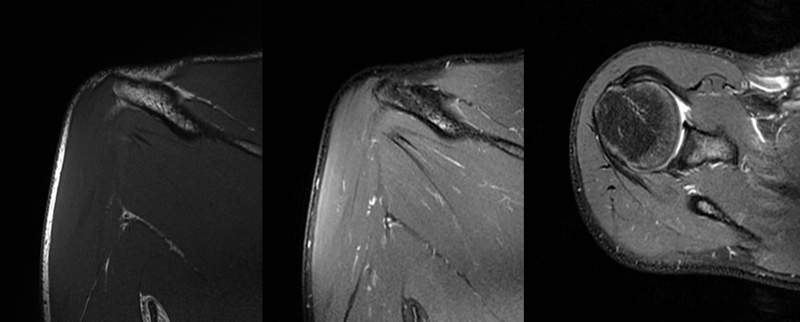

2、MRI检查

MRI目前是诊断肩袖疾病中最常用的检查,可以直观的观察肩袖肌腱。

图17 冈上肌

图18 冈下肌

图19 肩胛下肌

图20 小圆肌

图21 斜冠状位(临床常用)a.T2,b.T1

图22 斜矢状位 a.冈上肌出口,肩袖诊断不如斜冠状位;b.冈上肌及肌腹脂肪浸润成度,评估手术与否

图23 横断位a.正常肩胛下肌;b.肩胛下肌损伤

图24 a.肩袖全层撕裂;b.正常MRI

图25 巨大肩袖损伤(冈上肌)